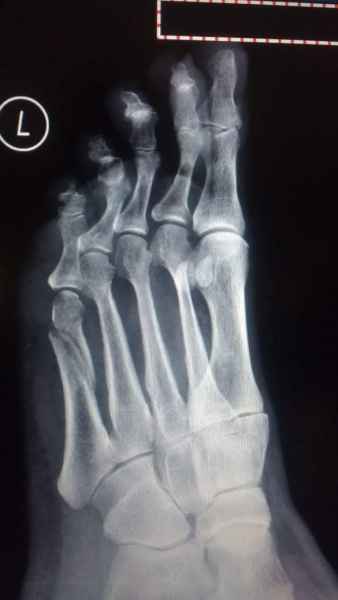

El pie es el órgano distintivo y característico de la especie humana, la única criatura que marcha erguida. El pie es una muy compleja estructura de arquitectura perfecta, adaptado a su función de apoyo, traslación, salto, con una riquísima sensibilidad que le permite detectar las más leves imperfecciones del suelo para estabilizar la marcha.

La marcha no solo es característica de la especie humana sino también de cada persona, y más aún varía según el estado de ánimo del momento. Una patología en los pies, se traduce en el rostro, en el ánimo, en el psiquismo. No sólo el dolor produce estos efectos, también un pie deformado o poco estético. En nuestra sociedad, la estética constituye un valor muy apreciado y estas alteraciones causan vergüenza fundamentalmente en las mujeres, que esconden en la playa sus pies en la arena y no pueden usar calzados elegantes.

Tanto la estructura del pie como su funcionalismo que es la marcha, pueden ser asiento y manifestación respectivamente de alteraciones locales ó sistémicas, por lo que su cuidadoso examen resulta de extrema utilidad diagnóstica.